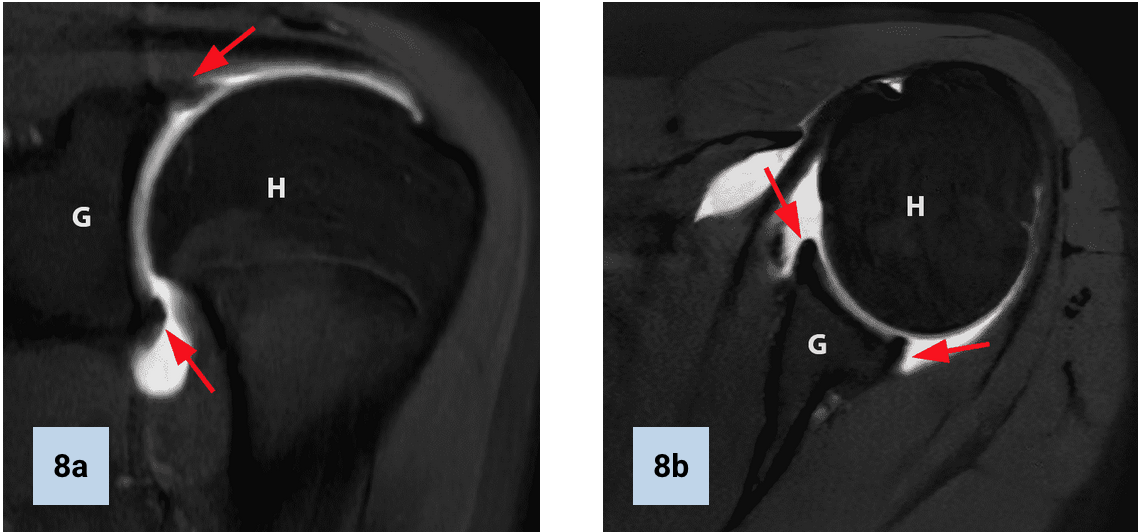

Bony Bankart lesion

• > 25% glenoid surface bone loss is an indication for surgery

• should comment on this in report

• Superior labral pathology is commonly assoicated with paralabral cyst formation

• Depending on cyst size and location can fuck up surrounding shit

• Can compress the suprascapular nerve (supplies supraspinatus or infraspinatus muscles)

• Spinoglenoid notch will affect infraspinatus alone